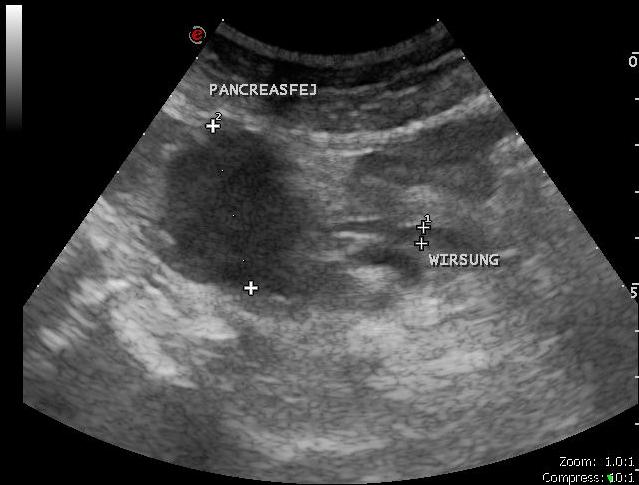

Idős hölgy sárgasággal

- Pancreas